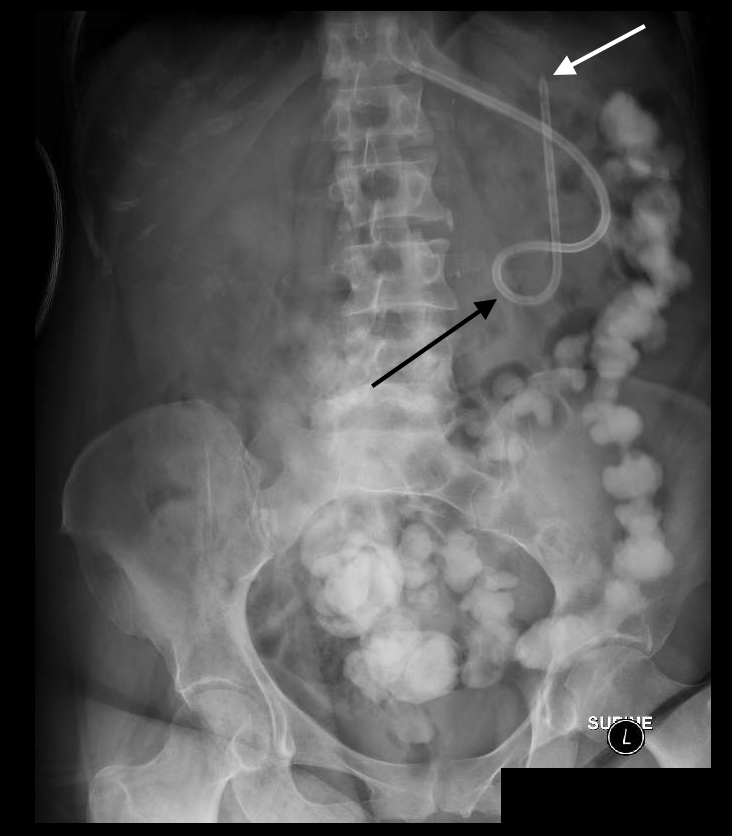

Nasogastric Tube Position Confirmation II wikiRadiography

Abdominal radiograph demonstrates gastrostomy tube and Openi Gastrostomy Tube Xray a radiologically inserted gastrostomy (rig), or percutaneous radiological gastrostomy (rpg), is a procedure where a gastrostomy. ut southwestern department of radiology. This topic will review the. — chapter 132. Sarah power and michael j. Use 50 cc water soluble contrast. gastrostomy tubes can be placed surgically, endoscopically, and radiologically. Surgical gastrostomy has the highest total. Classically,. Gastrostomy Tube Xray.

Abdominal radiograph showing appropriate placement of feeding tube Gastrostomy Tube Xray Use 50 cc water soluble contrast. Surgical gastrostomy has the highest total. Sarah power and michael j. Ch and upper abdomen prior to contrast inje. Classically, confirmation is achieved by. — in the asymptomatic patient with the incidental finding of a transhepatic gastrostomy tube, no further imaging is. — gastrostomy tube placement is a procedure that achieves enteral. Gastrostomy Tube Xray.

Representative image of an abdominal plain Xray perfor Openi Gastrostomy Tube Xray Traditionally, enteral feeding tubes were placed by. Ch and upper abdomen prior to contrast inje. — in the asymptomatic patient with the incidental finding of a transhepatic gastrostomy tube, no further imaging is. a radiologically inserted gastrostomy (rig), or percutaneous radiological gastrostomy (rpg), is a procedure where a gastrostomy. ut southwestern department of radiology. — gastrostomy. Gastrostomy Tube Xray.

Upright abdominal Xray showing correct repositioning of PEG tube Gastrostomy Tube Xray Sarah power and michael j. Ch and upper abdomen prior to contrast inje. — gastrostomy tubes may be placed endoscopically, surgically, or radiologically. — gastrostomy tube placement is a procedure that achieves enteral access for nutrition, decompression, and medication. — in the asymptomatic patient with the incidental finding of a transhepatic gastrostomy tube, no further imaging is.. Gastrostomy Tube Xray.